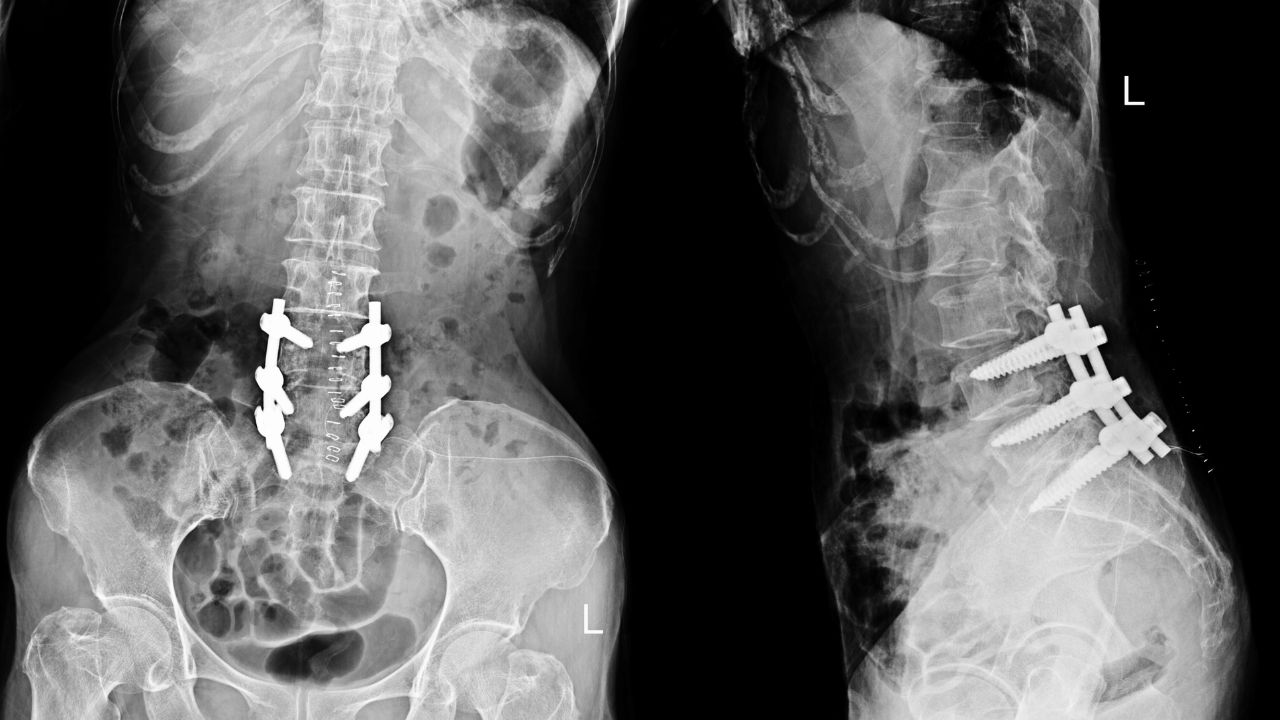

جراحی لامینکتومی نوعی عمل ستون فقرات است که در آن بخش پشتی مهره به نام لامینا برداشته میشود. این ساختار مانند قوسی استخوانی از نخاع محافظت میکند. با برداشتن لامینا، فضای کانال نخاعی افزایش یافته و فشار وارد بر نخاع یا ریشههای عصبی کاهش مییابد.

این روش معمولاً برای درمان اختلال اسکلتی عضلانی تنگی کانال نخاعی، فتق دیسک یا آسیبهای مشابه انجام میشود و بیشترین کاربرد آن در ناحیه کمری است. بااینحال در نواحی گردنی و صدری نیز ممکن است انجام شود.

در این مرحله، لامینا بهطور کامل یا جزئی برداشته میشود تا فشار از روی نخاع یا ریشههای عصبی کاهش یابد. همچنین در صورت وجود خار استخوانی، دیسک بیرونزده یا بافتهای آسیبدیده، آنها نیز خارج میشوند. گاهی در کنار لامینکتومی، عملهایی مانند دیسککتومی (برداشتن دیسک آسیبدیده)، فورامینوتومی (گشادکردن مسیر خروج عصب) یا فیوژن (جوشدادن مهرهها برای افزایش پایداری) نیز انجام میشود.